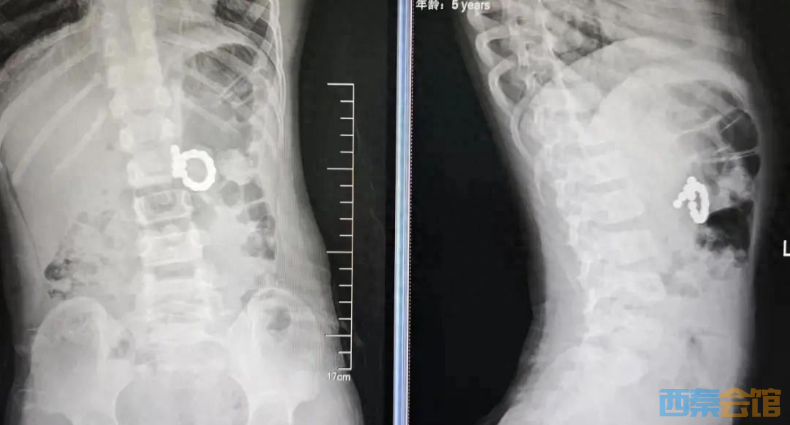

近日,苏州大学附属儿童医院成功救治一名误吞15颗磁力珠,引发胃与十二指肠对吸穿孔的5岁男童。牛牛(化名)在家中玩耍时,不慎将多枚彩色磁力珠当作“糖果”分次误食。家长发现后紧急送医,急诊X线提示:多枚消化道异物(15枚),但此时磁力珠已在牛牛消化道内相互吸附,强大的磁力跨越胃壁与十二指肠壁紧紧对吸,导致局部组织持续受压、缺血坏死,情况十分危急。